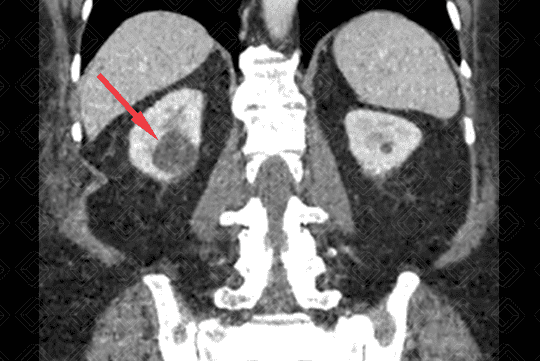

Texto alternativo para a imagem Figura 2. Créditos : Dra. Elazir Mota - Rio de Janeiro/RJ

Descrição da figura 2: Presença de diminuta lesão espontaneamente densa, no pólo inferior do rim esquerdo, compatível com cisto - Bosniak II (seta vermelha).